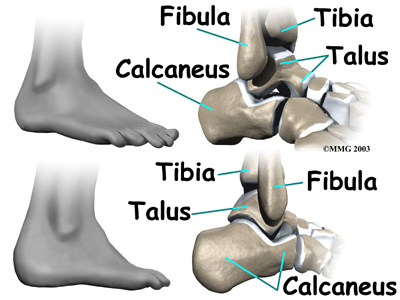

Bones and Joints

The ankle joint is formed by the connection of three bones. The ankle bone is called the

talus. The top of the talus fits inside a socket that is formed by the lower end of the

tibia (shinbone) and the

fibula (the small bone of the lower leg). The bottom of the talus sits on the heelbone, called the

calcaneus.

The talus works like a inside the socket to allow your foot to move up (dorsiflexion) and down (plantarflexion).